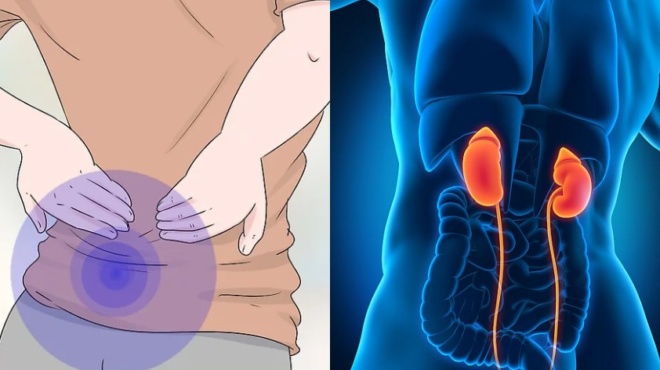

Μια σειρά παραγόντων μπορεί να προκαλέσει πέτρες στους νεφρούς, συμπεριλαμβανομένων των ακόλουθων διαιτητικών παραγόντων:

– Υψηλή πρόσληψη οξαλικού ασβεστίου από ορισμένα τρόφιμα

– Διατροφή υψηλής περιεκτικότητας σε πρωτεΐνες

– Υπερβολικό νάτριο (αλάτι)

– Αφυδάτωση, ή χαμηλή πρόσληψη υγρών

– Τα υψηλά οξαλικά τρόφιμα, όπως τα καρύδια, οι σπόροι, τα τεύτλα και το αλεύρι από φαγόπυρο, μπορούν να συμβάλουν στις πέτρες οξαλικού ασβεστίου, αν και αυτό δεν σημαίνει ότι πρέπει να τα αποκλείσετε από τη διατροφή σας εντελώς. Μια διατροφή με υψηλή περιεκτικότητα σε πρωτεΐνες μπορεί να συμβάλλει στον σχηματισμό λίθων φωσφορικού ασβεστίου. Η υψηλή πρόσληψη νατρίου (αλατιού) και η αφυδάτωση μπορεί να είναι παράγοντες σχηματισμού λίθων ουρικού οξέος και κυστίνης.